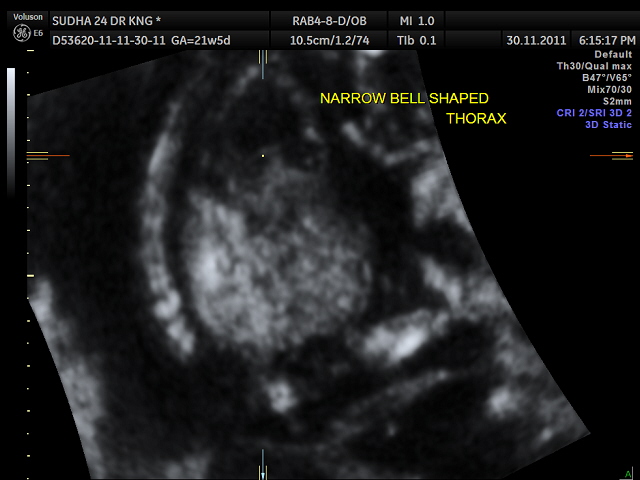

narrow , bell shaped chest , suggestive of pulmonary hypoplasia